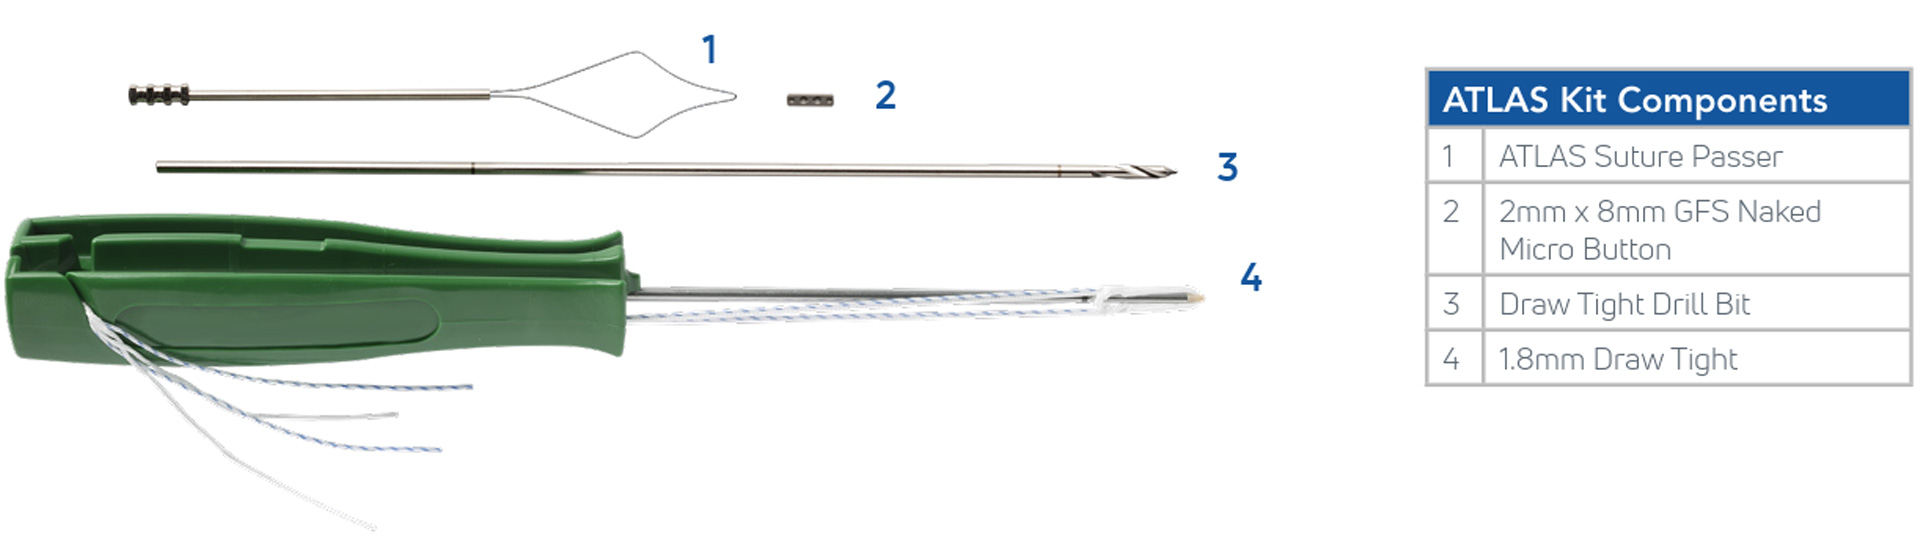

SISTEMA DE ARTROPLASTIA ANATOMICA DE LIGAMENTOS DEL PULGAR (ATLAS)

La técnica ATLAS está destinada a corregir la inestabilidad CMC del pulgar y facilitar un rápido retorno a la función mediante la colocación de fijaciones estables de anclaje basado en suturas en los sitios anatómicos de inserción del ligamento basal del pulgar.